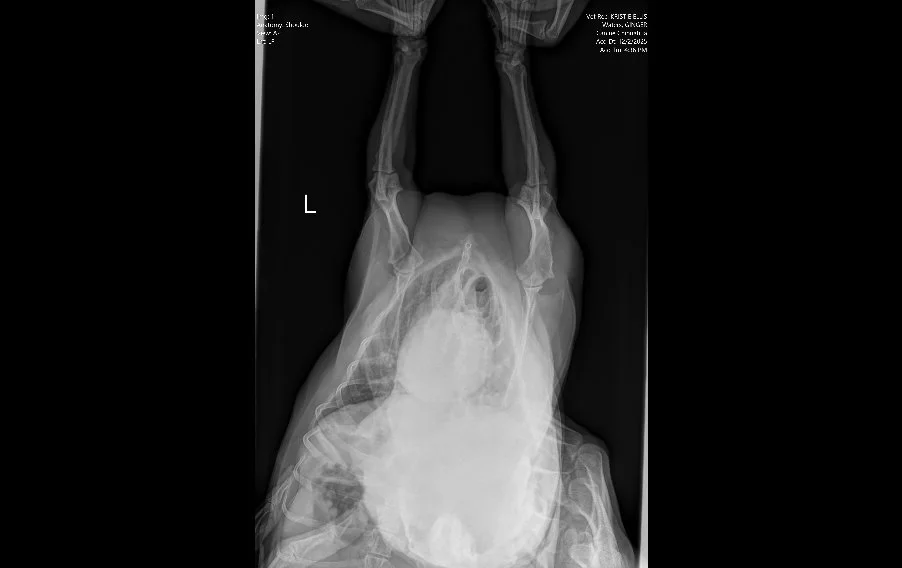

Image 1. Ventrodorsal radiograph of the thorax and forelimbs.

Radiographs (Images 1–4) of the left forelimb, including the carpus, elbow, and shoulder identified:

• Mild degenerative joint disease (arthritis)

• Decreased shoulder joint space

• No fractures, masses, or bone lysis

Based on these findings, Ginger was treated for osteoarthritis. However, her clinical progression did not match the imaging results.